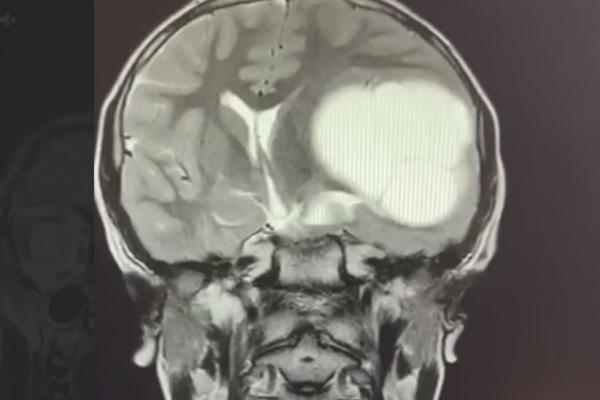

Фото: телеграм-канал BazaЧелябинские медики извлекли из мозга школьника 12-сантиметровый «клубок» ленточных червей. Причиной редкого заболевания скорее всего стали немытые руки, сообщает телеграм-канал Baza.

Сначала 12-летний Миша стал хуже учиться и жаловался на головную боль. Когда школьник стал неразборчиво писать и захромал, родители обратились в больницу. Там ребенку провели МРТ и диагностировали редкое заболевание – эхинококкоз головного мозга. Личинки червей проникают в мозг через кровоток, а заражение, как правило, происходит через грязные руки.

Мальчику провели сложную операцию в Челябинской детской областной клинической больнице и удалили образование в мозге. Сейчас ребенок восстанавливается, у него прошли головные боли и почти вернулась нормальная координация.